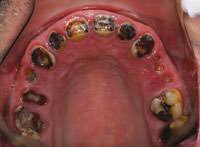

Full Mouth Extraction - Full Mouth Dental Implants Cost And Procedure - Full mouth extraction recovery process.. This little fella had to get a full mouth extraction from a lifetime of rotted teeth. Looking to get full upper teeth extracted then dentures … read more. Gingivalis in 15 of 16 and 8 of 16 previously positive patients using. Dentistry by tim kosinski dds, bingham farms mi. In the case where a full mouth extraction is necessary, know that your cat can still lead a happy and healthy life including properly eating.

Full recovery from the surgery can take about a week, sometimes more, depending upon a patients age and if they undergo a full or. You might come across a bump or sore in your mouth that doesn't seem to heal. Tim kosinski performs atraumatic full mouth extractions utilizing the physics forceps. Для просмотра онлайн кликните на видео ⤵. Full mouth disinfection typically refers to an intense course of treatment for periodontitis typically involving scaling and root planing in combination with adjunctive use of local antimicrobial adjuncts to periodontal treatment such as chlorhexidine in various ways of application. He was adopted and is living his best life now! Day 4 and 5 full mouth extraction. I am 55yo and have only 20 teeth in my mouth. It's to be expected that a full mouth extraction will take a little longer than extracting just one tooth. I am on medications that i need to take the rest of my life that are deterioirating my. O after the procedure, you might notice slight bleeding. A lot of people are asking why someone would need a full mouth extraction (fme) like this. Our cat had a full mouth extraction when he was 5 years old.

Day of surgery full mouth extractions. Full mouth dental implants are your best lifelong investment. I am 55yo and have only 20 teeth in my mouth. In the case where a full mouth extraction is necessary, know that your cat can still lead a happy and healthy life including properly eating. Earlier studies with low number of patients have shown. He had in fact 3 different extractions. Atraumatic extraction procedure performed with the physics forceps by golden dental solutions. Full recovery from the surgery can take about a week, sometimes more, depending upon a patients age and if they undergo a full or. Full mouth extraction day 3. How long before pain goes away from full mouth teeth extraction? This little fella had to get a full mouth extraction from a lifetime of rotted teeth. · the day of your surgery. Full mouth reconstruction, rehabilitation and restoration are terms often used interchangeably to describe the process of rebuilding or simultaneously restoring all of the teeth in both the upper and.

After Multiple Tooth Extractions Oral Surgery Richmond Va from i.ytimg.com This little fella had to get a full mouth extraction from a lifetime of rotted teeth. How long before pain goes away from full mouth teeth extraction? Dentistry by tim kosinski dds, bingham farms mi. This is just a little video about my experience with a full mouth extraction. While having all of your teeth pulled at once can seem like something nobody wants to go through, a lot of the time it's for your best interest and to provide you. The vet says his left side is worse than the right but he needs a full mouth extraction. Extractions provided clinical resolution of oral discomfort in about 80 percent of cases. Day 4 and 5 full mouth extraction.